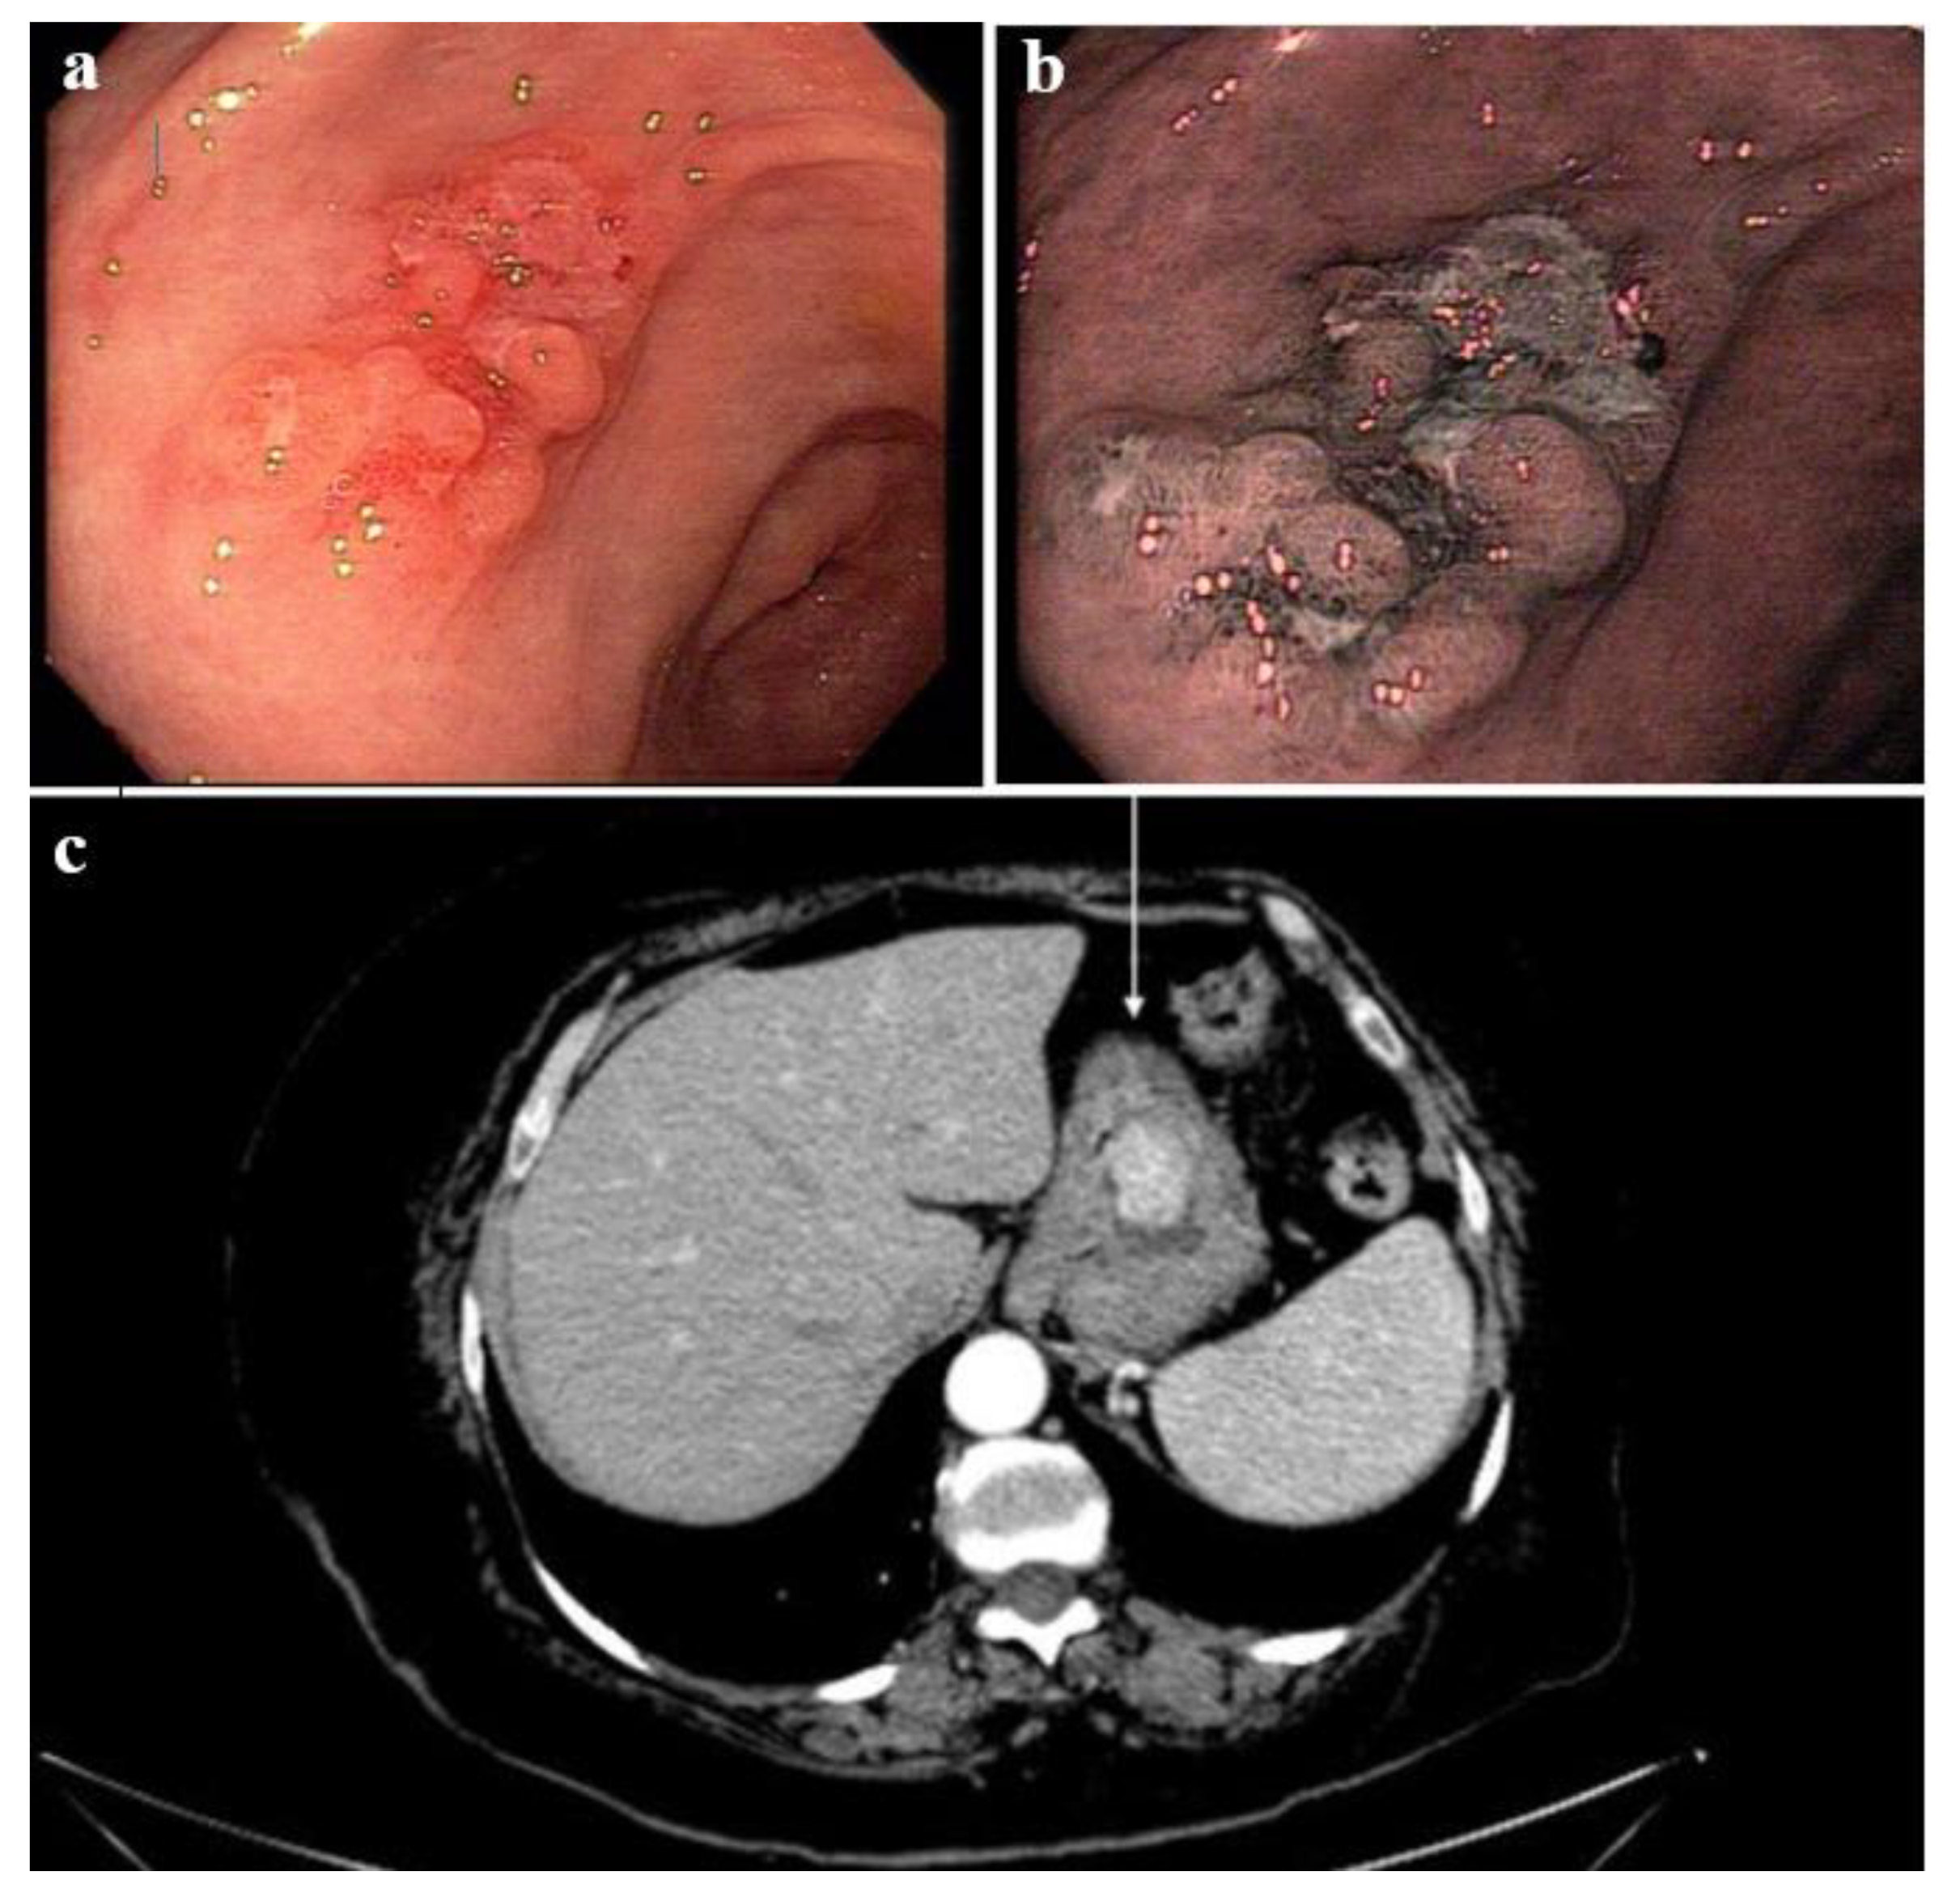

3. Results